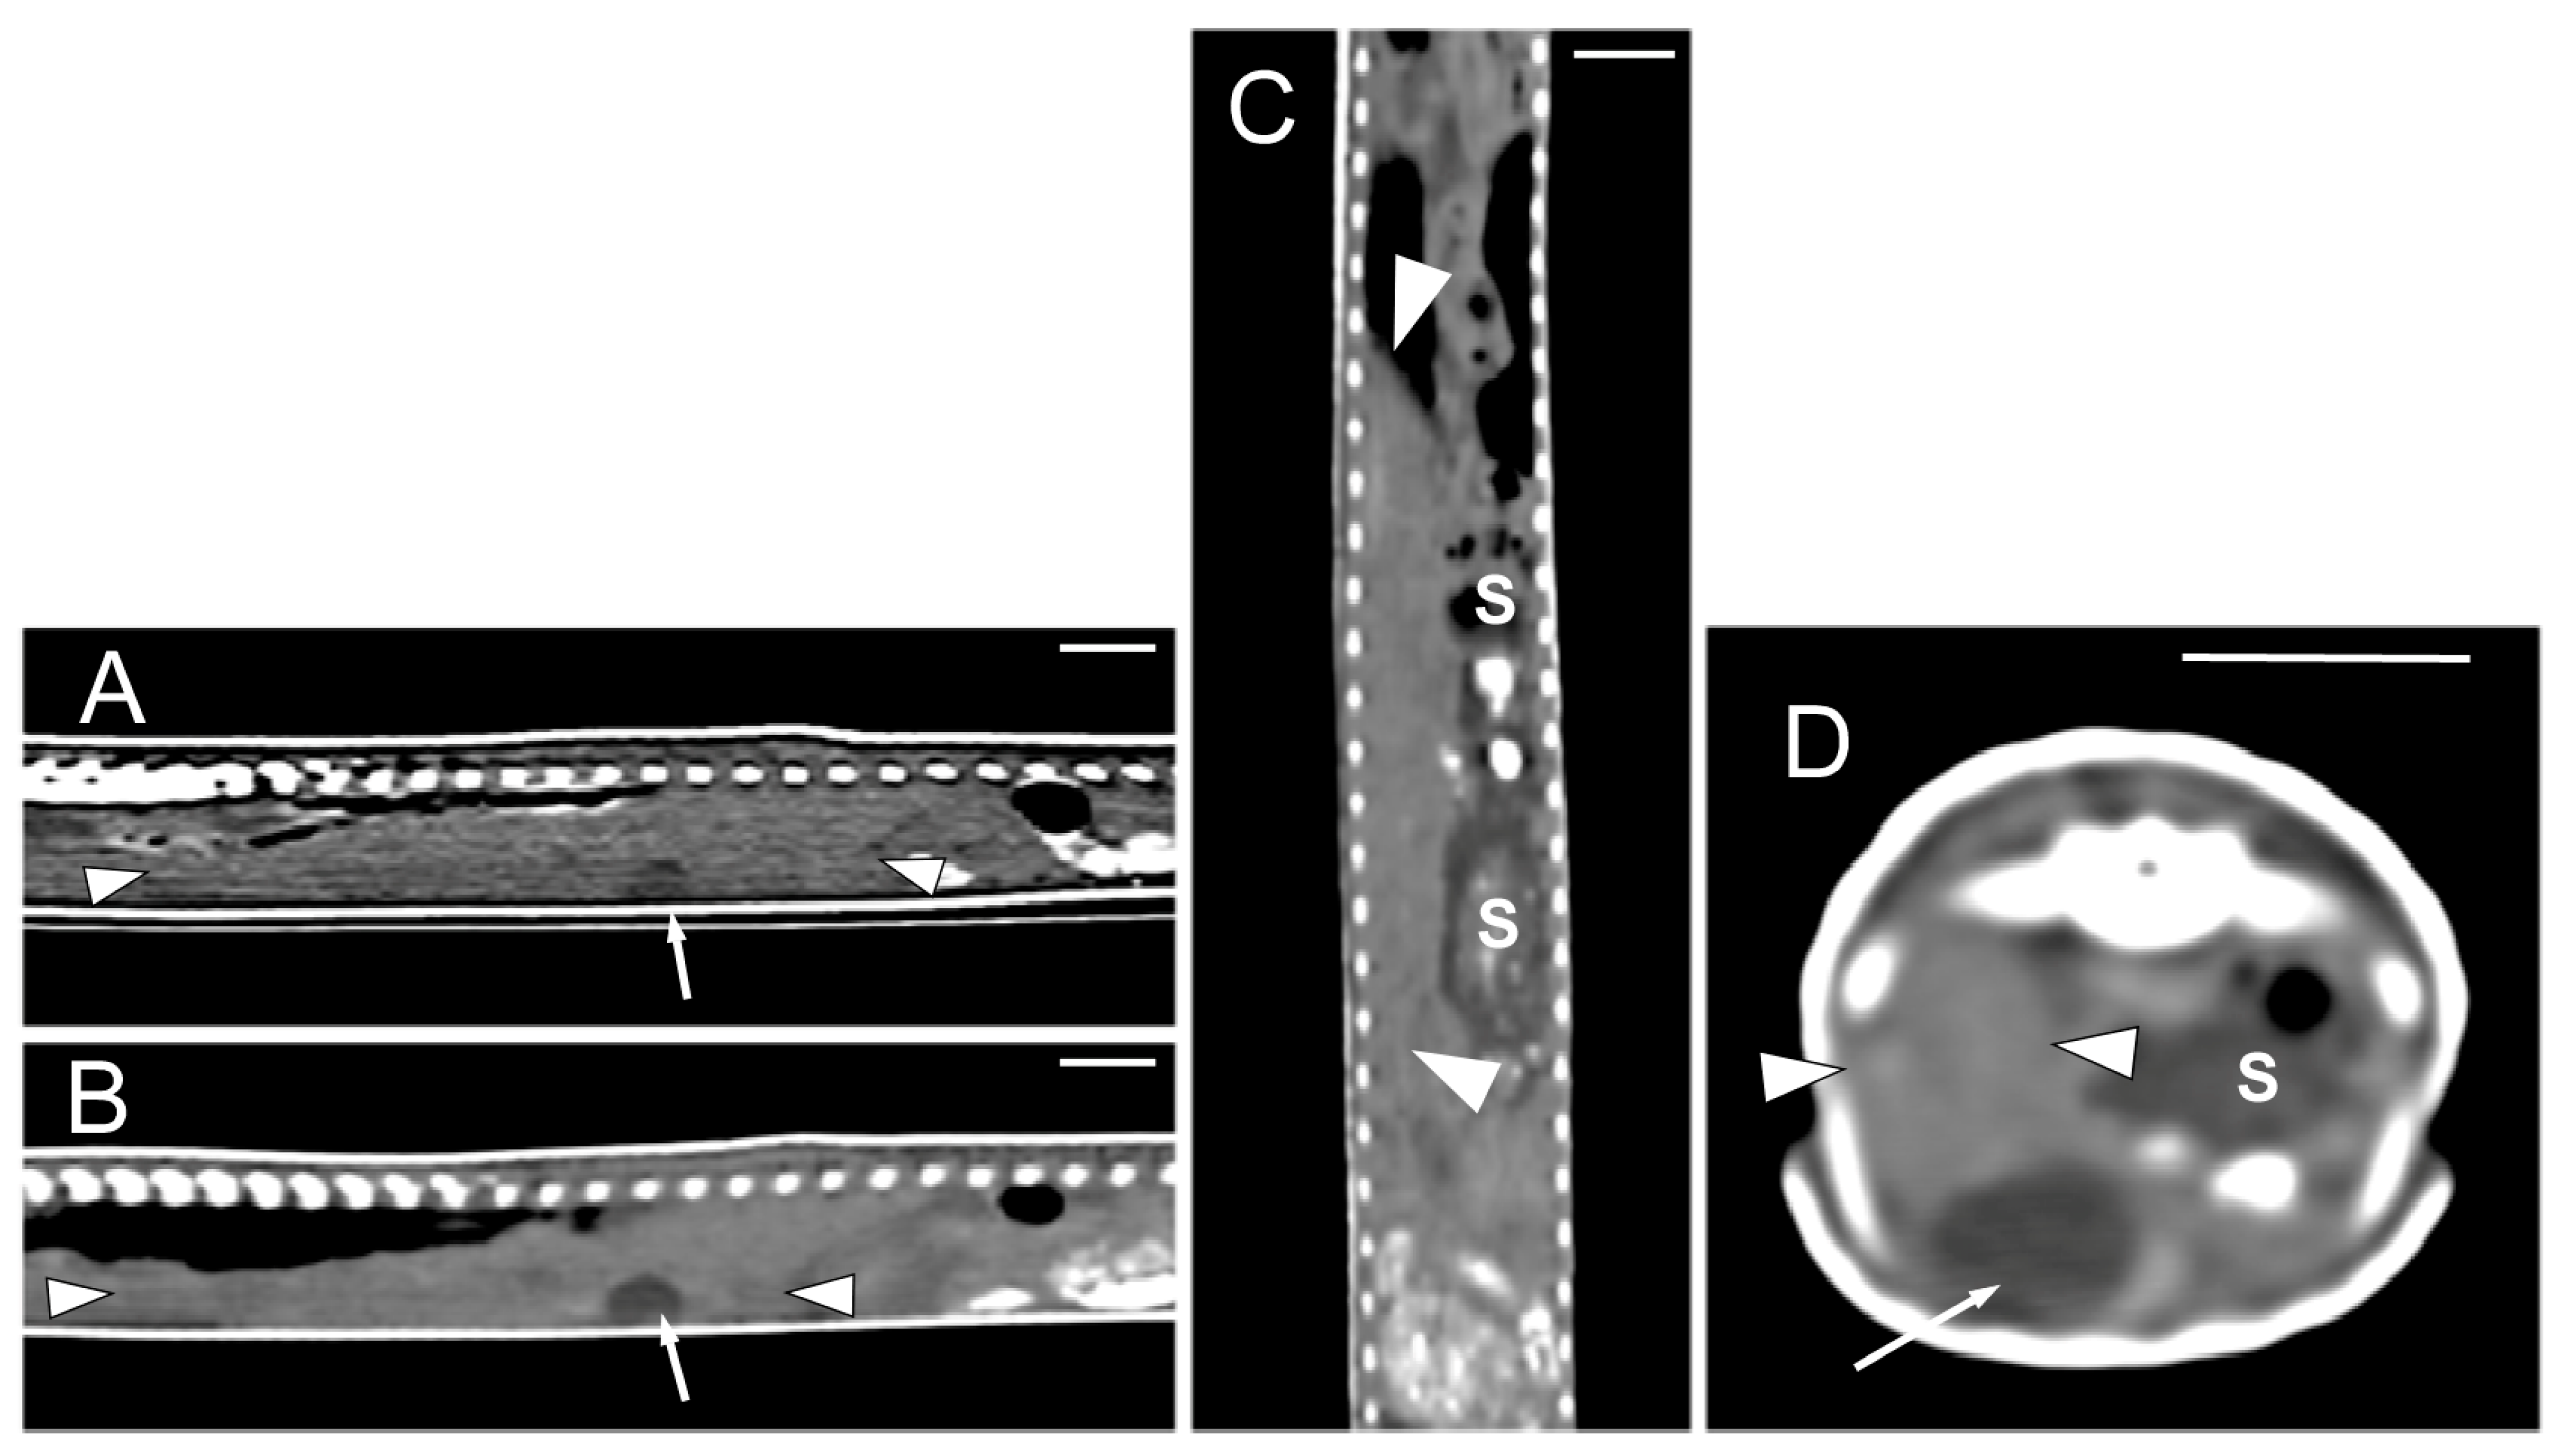

Concerning the CT images, the bifurcation of the trachea into the main bronchi was most clearly observed in the transverse plane (Figure 8A). The two lungs appeared as elongated structures with a reticular hypoattenuating area around an air-filled cavity. The distinction between the hypoattenuating area and just air was more distinctly identified in the transverse and dorsal planes using a postprocessing lung algorithm (Figure 8B,C). The 3D volume rendering using a postprocessing airways algorithm detailed the trachea and lungs (Figure 8D,E). Between the lungs, it was possible to identify those esophageal segments containing gas. On the contrary, those esophageal segments without intraluminal gas were indistinguishable from the surrounding soft tissues. The transverse and dorsal planes were the most useful for recognizing the esophagus (Figure 9). The liver appeared as an elongated organ with soft tissue attenuation located ventral to the caudal midsection of the lungs, on the right side of the stomach. Its margins were not well defined. The gall bladder was identified in the ventral part of the coelomic cavity as a hypoattenuating small oval structure surrounded by the hepatic parenchyma (Figure 10A). The differentiation between the gall bladder and the hepatic parenchyma was more evident in the postcontrast studies (Figure 10B–D). As in the case of the esophagus, the stomach and the small and large intestines were easily distinguished when containing intraluminal gas (Figure 11A) or hyperattenuating content (residual ingesta) (Figure 11B). The small and large intestines were located just caudal to the liver and the stomach, occupying approximately the caudal third of the coelomic cavity. The spleen and pancreas could not be identified when using CT.

Figure 8.

The CT images of Pseudopus apodus in the transverse (A,B) and dorsal (C) planes, and the 3D volume rendering showing the airways (D,E). Image (A) was obtained with a soft tissue algorithm and shows the main bronchi bifurcation (white arrow), while images (B,C) were postprocessed using a lung algorithm and show the peripheric hypoattenuating area (black arrowheads) around an air-filled cavity. The images (D,E) were postprocessed using the 3D volume rendering with airways algorithm and offer a detailed representation of the trachea (tr) and lungs (L). Bar = 10 mm.

Figure 9.

The CT images of Pseudopus apodus in the transverse (A) and dorsal (B) planes showing segments of the esophagus (arrowheads) with intraluminal gas. The esophagus is located between the lungs (L). Bar = 10 mm.